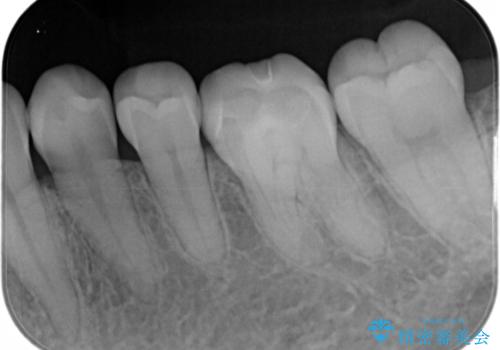

- 大きく口を開けると目立つ銀歯のやり替えをご希望された患者様です。適合のよいセラミックインレーで補綴することで、将来的な虫歯発生のリスクを最小限に抑え、機能面でも安心して使っていただけるようにしました

適合不良の補綴物は二次的な虫歯発生のリスクが高まります。

自費診療で用いられる材料は保険適応の材料に比べて、より精密で適合の良い被せ物作ることができるため、長期的な虫歯のリスクを大幅に減らすことが可能です。